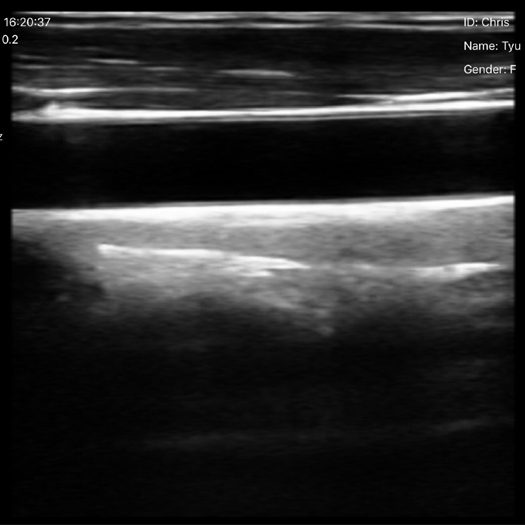

El ecógrafo inalámbrico portátil de alta rentabilidad es la herramienta ideal para estudiantes de medicina, enfermería, kinesiología, veterinaria y carreras del área de la salud. Gracias a su bajo costo, es accesible como la compra de un teléfono celular, permitiendo que más personas puedan entrenar con tecnología real sin depender de los equipos institucionales.

Es una herramienta ideal para quienes buscan formarse en ecografía de manera práctica, económica y accesible, brindando imágenes de buena resolución para entrenar la identificación de estructuras anatómicas, técnicas de exploración y procedimientos básicos.

Exploración Doppler color en clínicas y punto de atención.

Monitoreo de vasos y flujo sanguíneo en entornos clínicos y educativos.